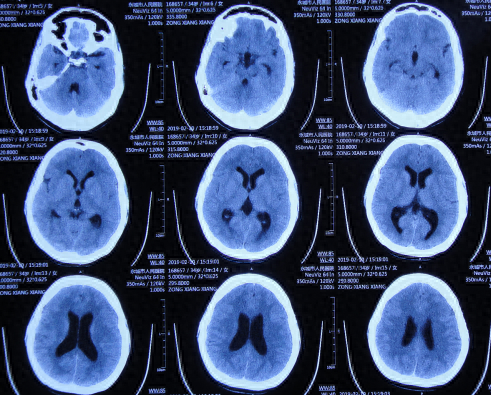

一、李小勇脑脊液科入院前病史

患者2019年2月初,因数次出现发作性黑蒙,2019年2月10日就诊于当地的河南省永城市某医院,查头颅CT未见明显异常(图-1);次日再查头颅核磁、颈椎核磁(图-2、图-3)后发现小脑扁桃体下疝畸形合并脊髓空洞。

图-1:2019年2月10日头颅CT